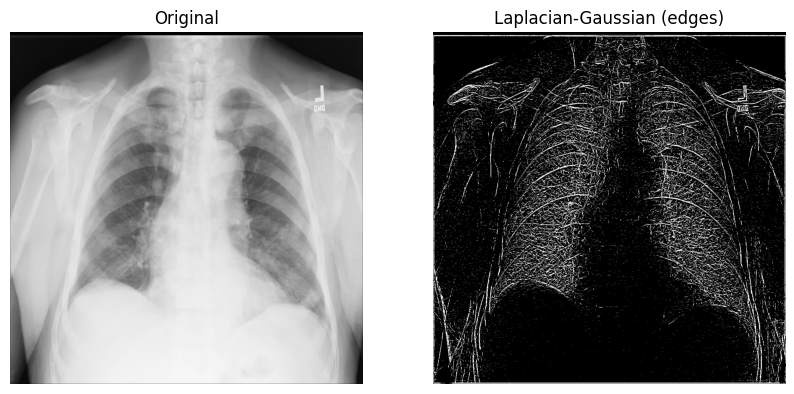

使用拉普拉斯-高斯、高斯梯度、Sobel 和 Canny 过滤器

让我们从使用 拉普拉斯 过滤器(“拉普拉斯-高斯”)开始,该过滤器使用 高斯 二阶导数。这种拉普拉斯方法侧重于值快速变化的像素,并与高斯平滑相结合以去除噪声。让我们看看它在分析 2D X 射线图像中的应用。

- 拉普拉斯-高斯过滤器的实现相对简单:1)从 SciPy 导入

ndimage模块;2)使用带有 sigma(标量)参数的scipy.ndimage.gaussian_laplace()函数,该参数影响高斯滤波器的标准差(在下面的示例中,您将使用1):

from scipy import ndimage

xray_image_laplace_gaussian = ndimage.gaussian_laplace(xray_image, sigma=1)

显示原始 X 射线图像和应用拉普拉斯-高斯过滤器后的图像:

fig, axes = plt.subplots(nrows=1, ncols=2, figsize=(10, 10))

axes[0].set_title("原始图像")

axes[0].imshow(xray_image, cmap="gray")

axes[1].set_title("拉普拉斯-高斯(边缘)")

axes[1].imshow(xray_image_laplace_gaussian, cmap="gray")

for i in axes:

i.axis("off")

plt.show()